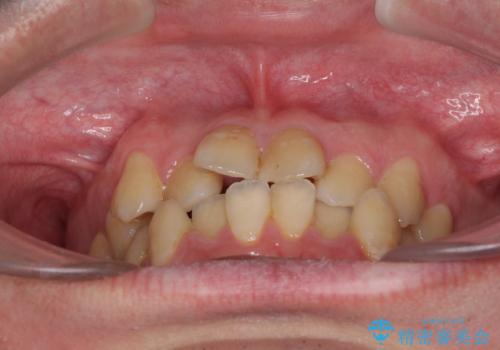

- 上下のデコボコと前歯のクロスバイトを改善したいとのことで来院された患者様です。

マウスピース矯正での自己管理には自信がないとのことで、ワイヤー装置による矯正治療を行うこととしました。

デコボコの程度は強かったのですが、口元の突出感はなかったため、非抜歯矯正としました。